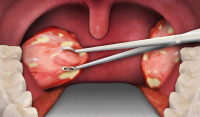

Слинні залози у нашому організмі відповідальні за вироблення слини – рідини, яка важлива для травлення та очищення порожнини рота, захисту зубів від мікроорганізмів. Однак у них можливі запальні процеси, утворення різного ступеня інтенсивності та вираженості.